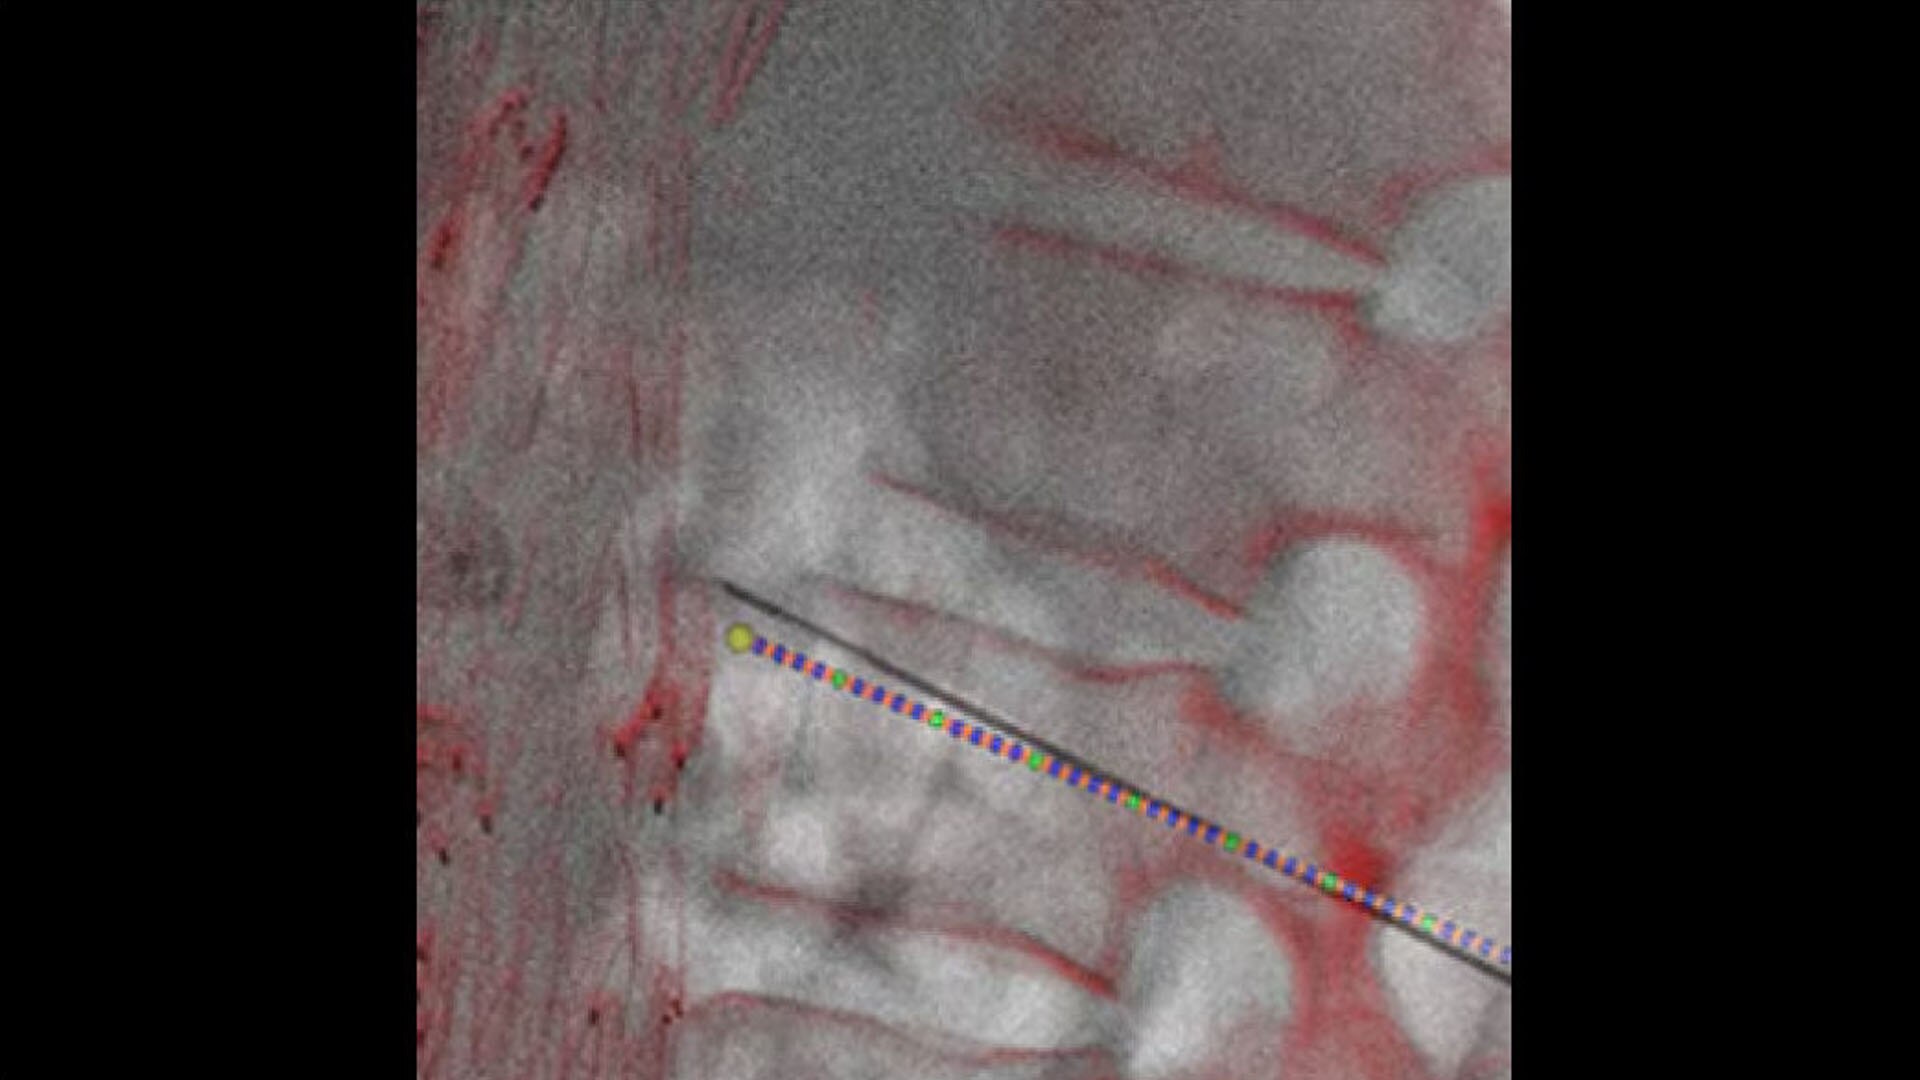

Guide

3D fusion guidance all at table side

Visualize and correct mis-registrations in both translation and rotation.

hero_sticky_scrolling_2-ci-en